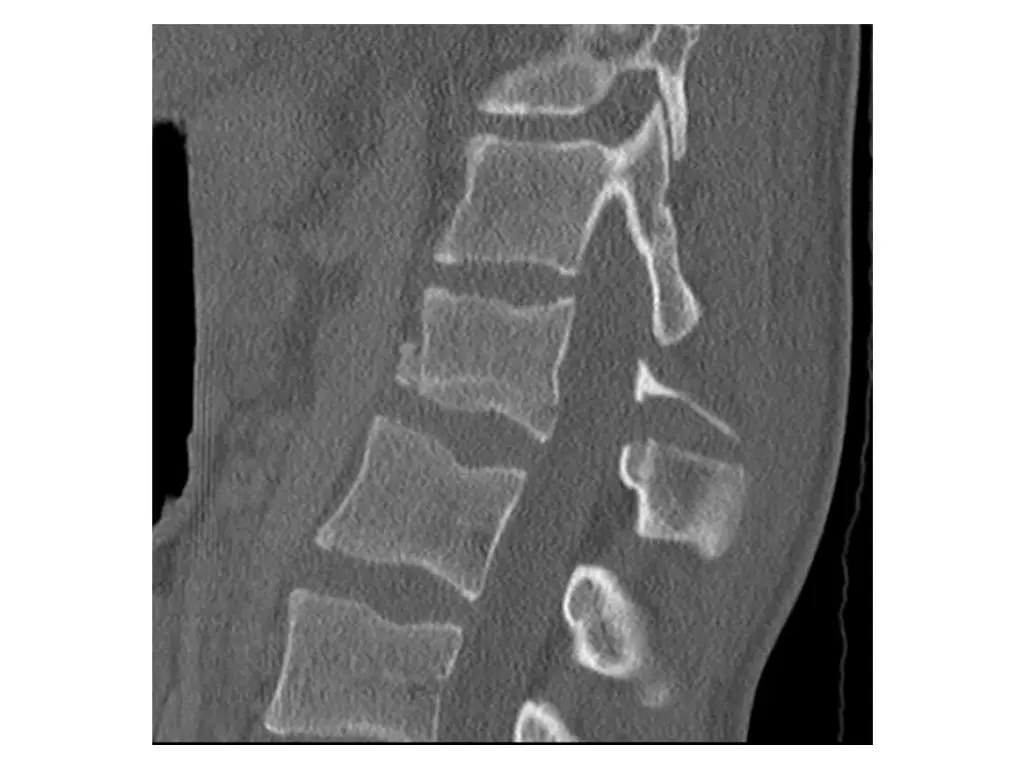

Imaging (Case 1) Midsagittal CT scan Parasagittal CT scan Axial CT scan Midsagittal STIR MRI scan

Imaging (Case 2) Lateral XR Midsagittal CT scan Parasagittal CT scan Axial CT scan

Imaging (Case 3) Lateral XR Midsagittal CT scan Parasagittal CT scan